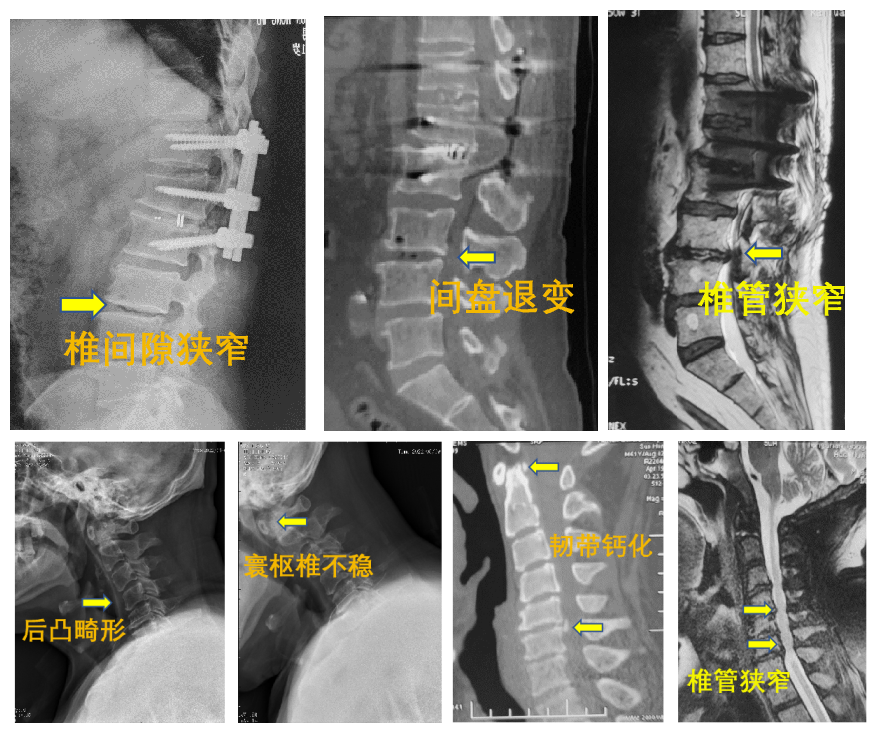

来院后,患者已无法下地行走,双腿也很难抬离床面,翻身只能靠别人帮忙。同时他告诉孙振兴,最近半月来还新发了腰痛,放射至双下肢,疼痛范围自大腿外侧延伸至小腿外侧和脚掌,双上肢也出现无力和麻木疼痛的症状。孙振兴判断,患者除神经根损伤之外,还存在脊髓损伤。在完善相关检查的基础上,孙振兴联合神经内科副主任冯新红进行神经电生理检查,果然,结果提示上下肢周围运动神经存在损害。综合所有影像学检查结果,孙振兴确诊患者存在寰枢椎不稳、颈椎管狭窄、颈椎后凸畸形、腰椎管狭窄,集多种脊柱疾病于一身。

患者术前影像